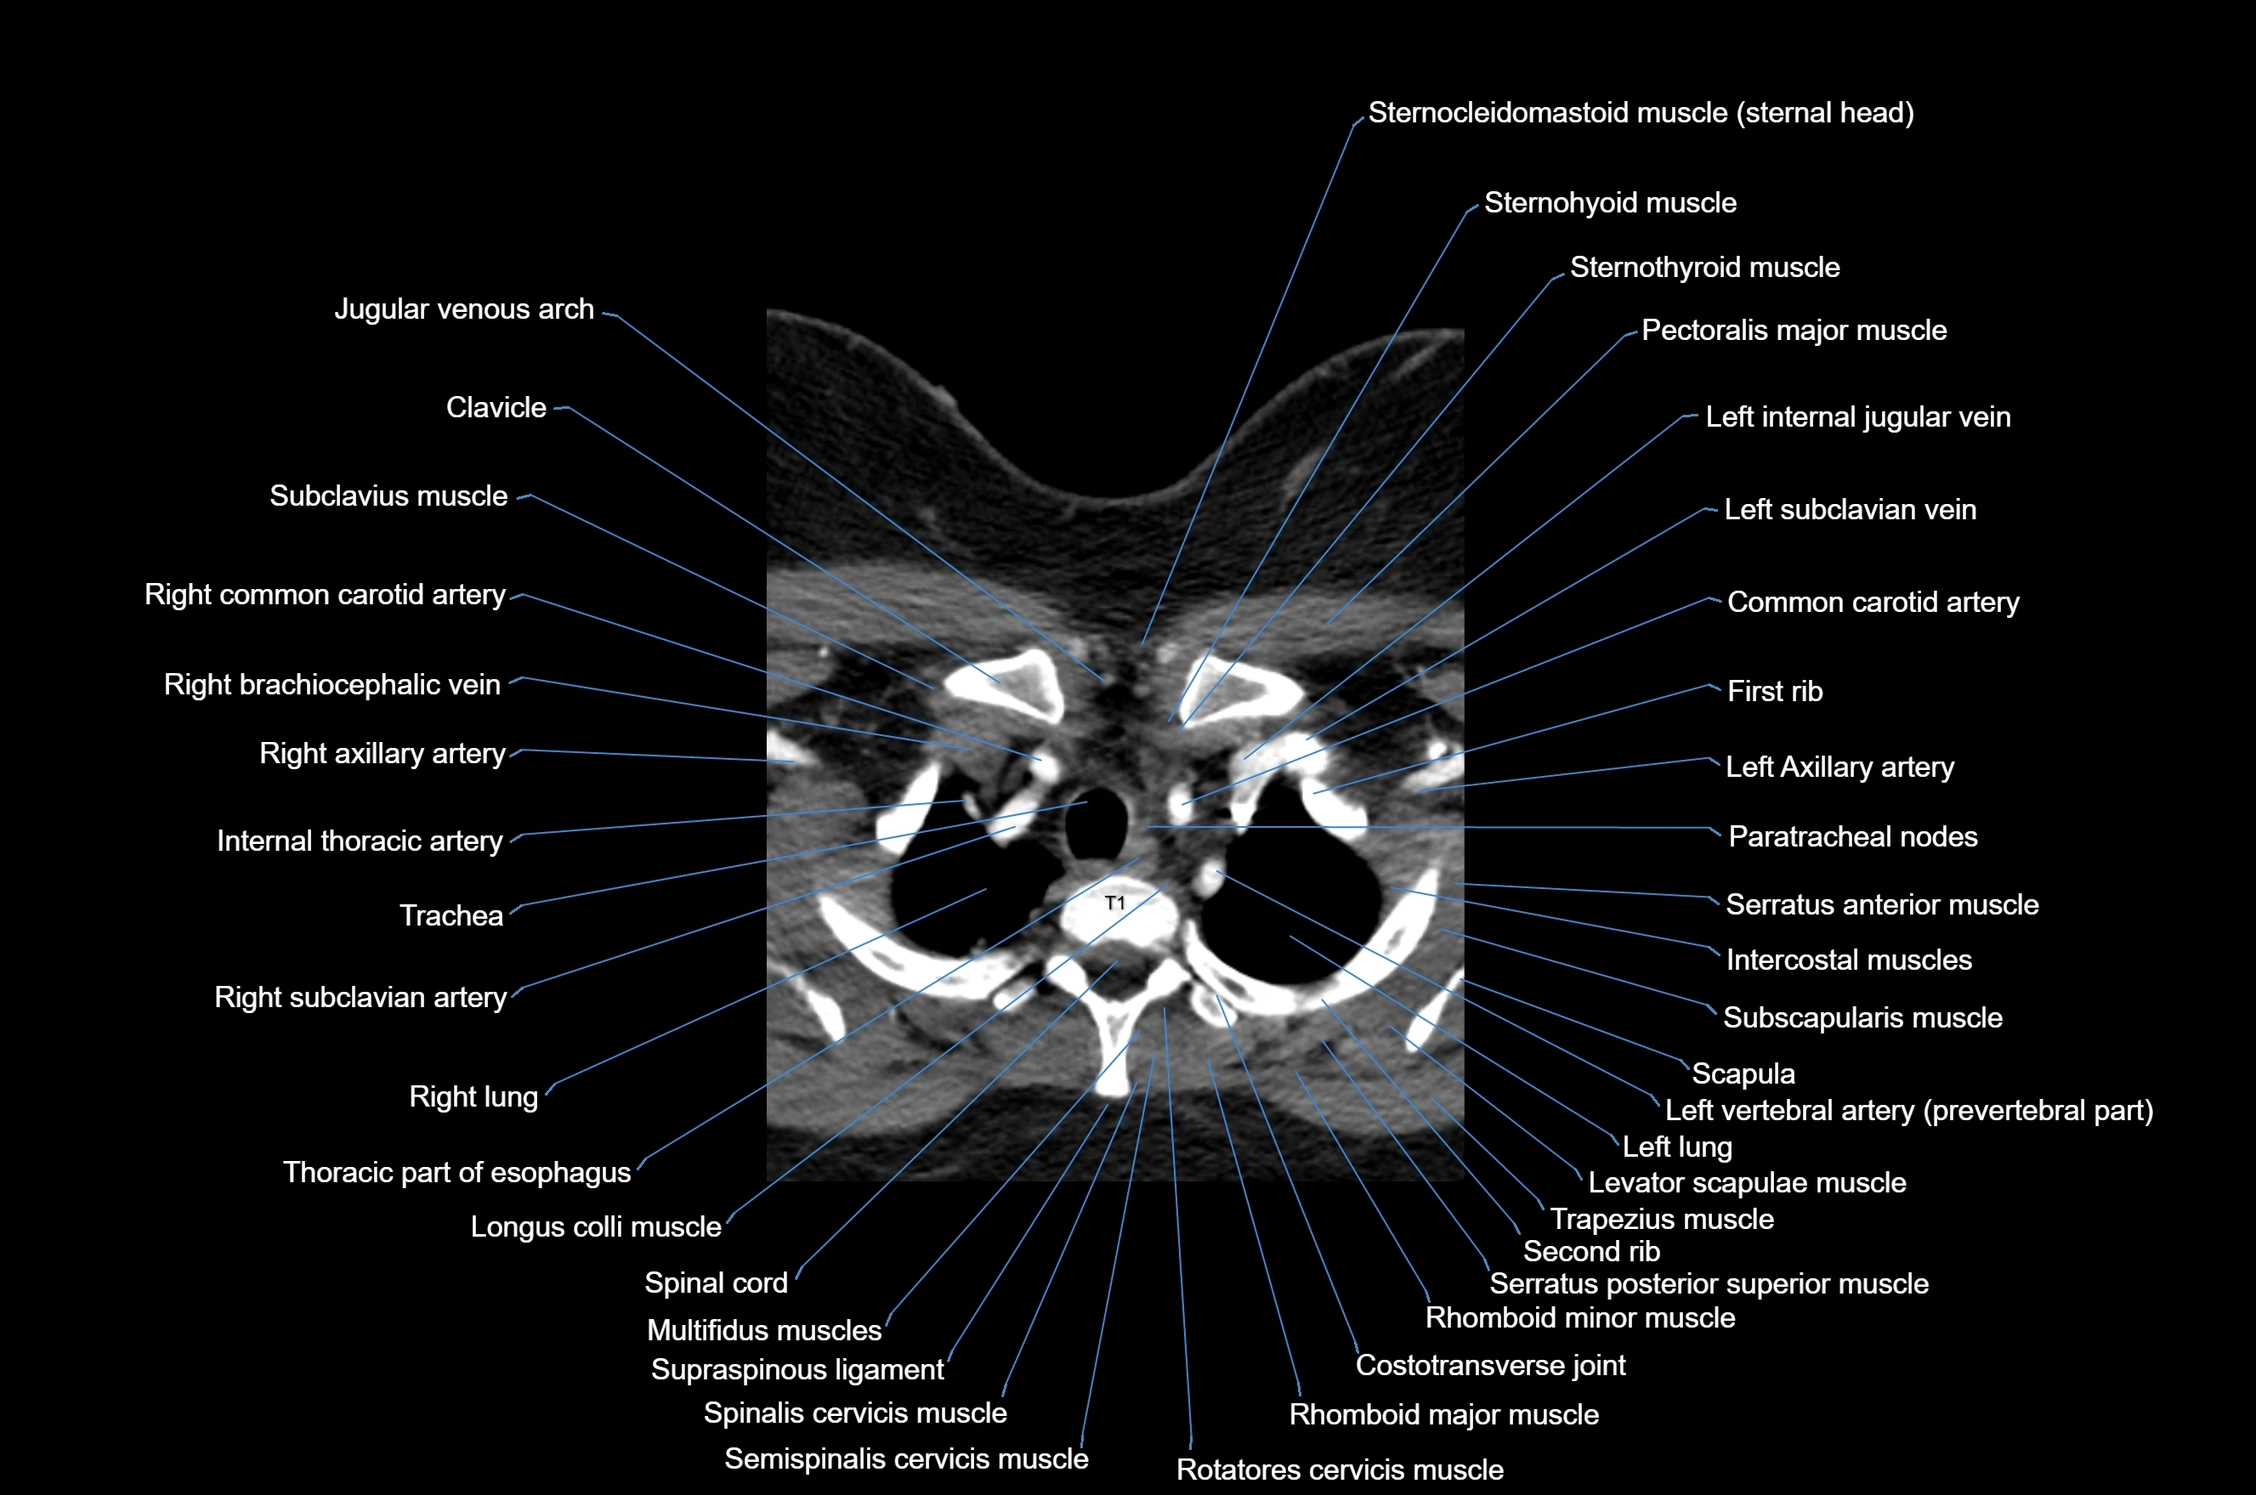

- Axillary artery

- Clavicle

- Costotransverse joint

- First rib

- Intercostal muscles

- Internal thoracic artery

- Left brachiocephalic vein

- Left common carotid artery

- Levator scapulae muscle

- Longus colli muscle

- Multifidus muscles

- Paratracheal lymph nodes

- Rhomboid major muscle

- Rhomboid minor muscle

- Right subclavian artery

- Rotatores cervicis muscle

- Semispinalis cervicis muscle

- Serratus anterior muscle

- Serratus posterior superior muscle

- Spinal cord

- Spinalis cervicis muscle

- Supraspinous ligament

- Thoracic part of esophagus

- Trachea

- Trapezius muscle